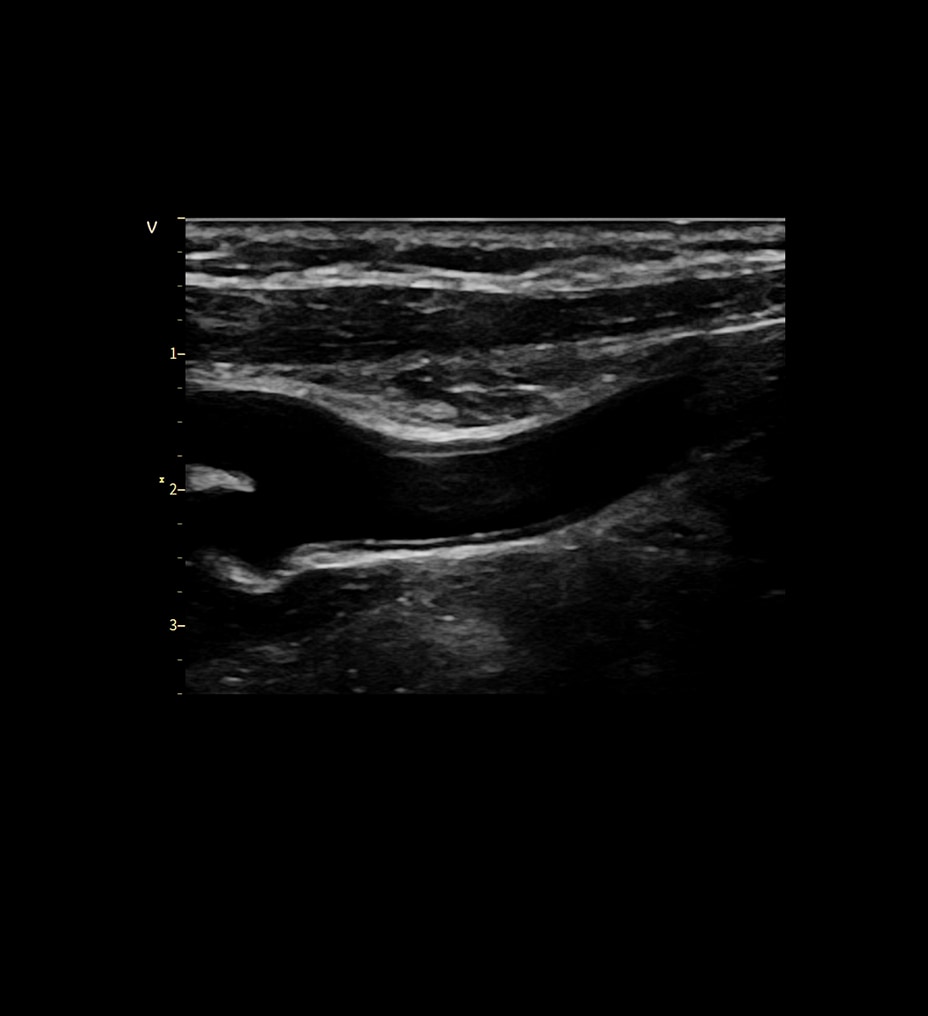

Visualize more anatomy in a single scan with Virtual Convex

This tool provides a wide field of view so users can visualize more large anatomy structures in a single scan.

Easily see the anatomy you need to see with Venue View

Supporting diagnostic confidence by constructing a panoramic image from individual frames, Venue View allows you to view up to 60cm of anatomy being scanned with anatomical relationships in one view.2